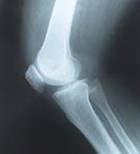

לא חייבים לחיות עם מפרקי ברך שחוקים, כואבים ומציקים....